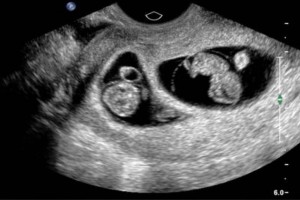

Diplomados en Ultrasonografía